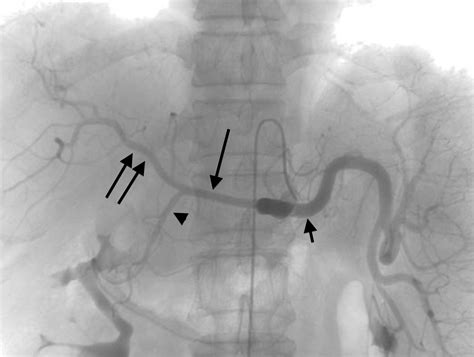

Diagnosis typically begins with a physical examination, followed by imaging studies. Physicians commonly utilize Duplex Ultrasound as a primary screening tool because it is non-invasive and effective at measuring blood velocity within the mesenteric arteries. More definitive imaging, such as a CT Angiography (CTA) or Magnetic Resonance Angiography (MRA), provides detailed, high-resolution views of the arterial anatomy, allowing surgeons to plan potential interventions.

• Angioplasty and Stenting: A minimally invasive procedure where a small balloon is used to open the artery, and a stent is placed to keep it open. This is often the preferred first-line treatment for its shorter recovery time.

• Bypass Surgery: A more traditional open surgical approach where a graft (a synthetic tube or a vein from the body) is used to redirect blood flow around the blocked segment of the artery.